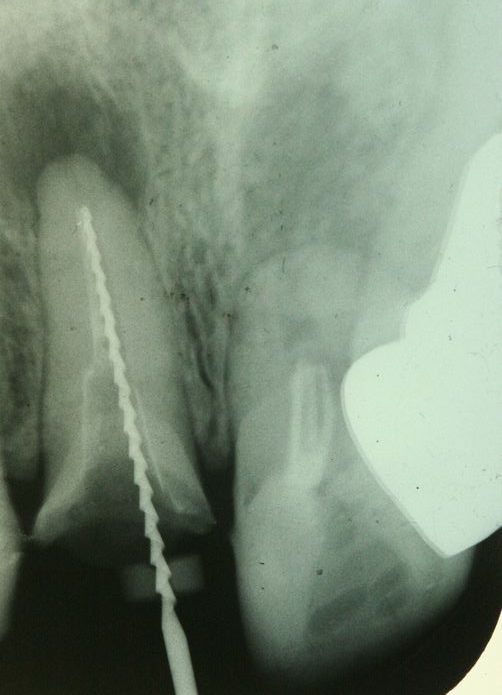

今日患者さんの了解が取れたのでレントゲン画像をUPしておきます。

歯の全長は実測17mmです、レントゲンから骨内にある歯根長を推測すると約5mm弱くらいだと思います。

問題なく何でも咬めるそうです。

参考になさってください。

画像1 治療前(向かって右の歯)

画像2 根管充填後